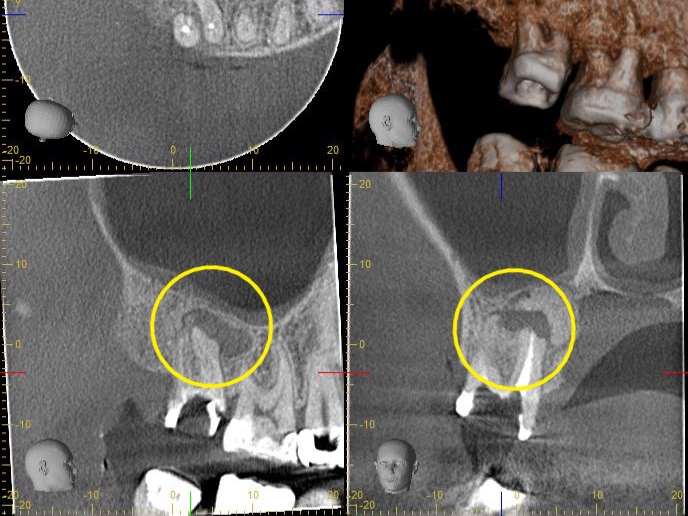

診断:CTによる精密検査で見つかった複雑な感染源

CTでしっかりと診断を行ったところ、とても深刻な状況でした。根管治療が重要ですが、それだけでは完全な治癒が望めない場合もあり、歯槽骨の再生を促す外科的処置が必要になることもあります。

根尖病変によりCT上で黒く写っていた部分が白っぽくなっているのがわかりますか?

溶けていた部分の歯槽骨が回復しているということです!

また、上顎洞の肥厚は収まり、頬側の歯槽骨もくっきり映っています。予想以上に歯槽骨が回復しているので、今後外科的処置をしなくても良いのではないかと判断しました。大きなダメージがあった歯なので補綴物を入れた後も欠かさずに経過観察を行い、少しでも長くご自身の歯で生活して頂きたいと思います。